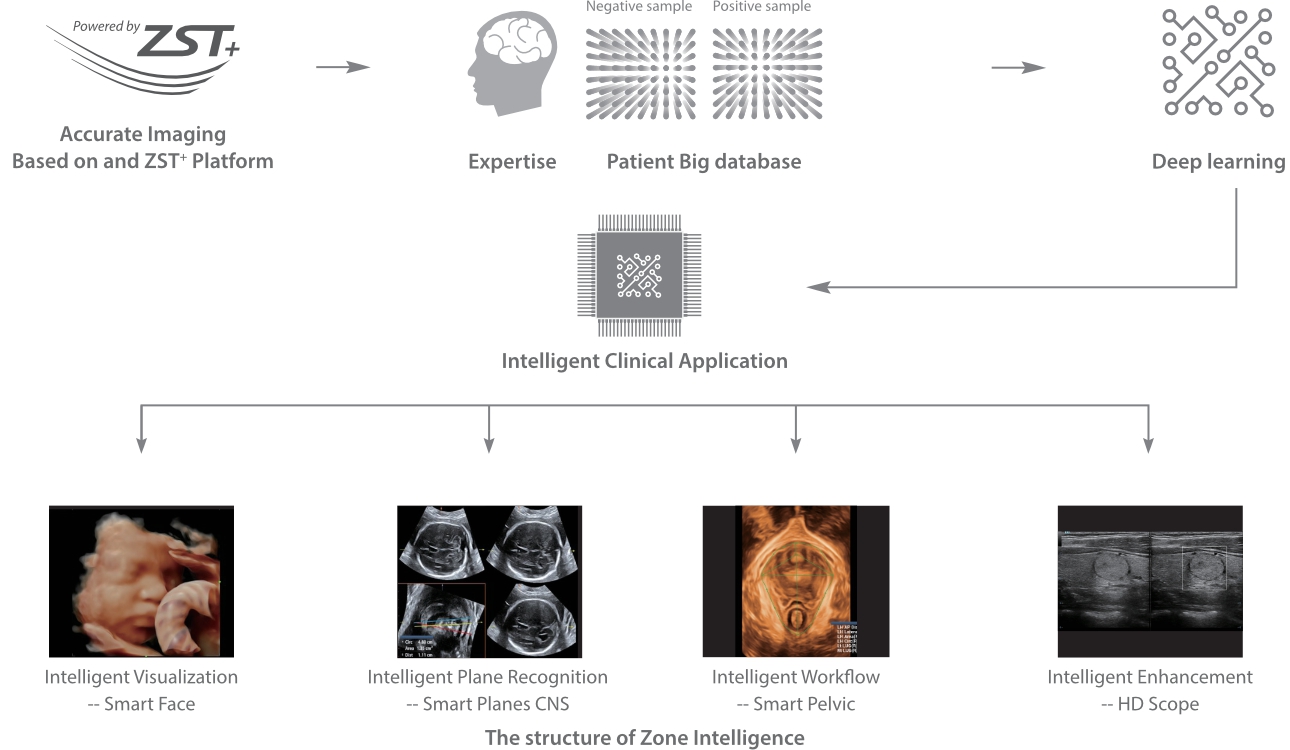

With Zone Intelligence

Since the company was founded, Mindray has been continuously exploring new ways to improve diagnostic confidence. Powered by the most revolutionary ZONE Sonography? Technology, Resona 7ŌĆÖs new ZST+ platform brings ultrasound image quality to a higher level by zone acquisition and channel data processing.

As well as the premium level image quality, Resona 7 also enhances clinical research capabilities with the revolutionary V Flow for vascular hemodynamic evaluation, and the most intelligent plane acquisition from 3D datasets for fetal CNS diagnosis. Combining the most intuitive gesture-based multi-touch operation and all the essential clinical features, Resona 7 is truly leading new waves in ultrasound innovation.